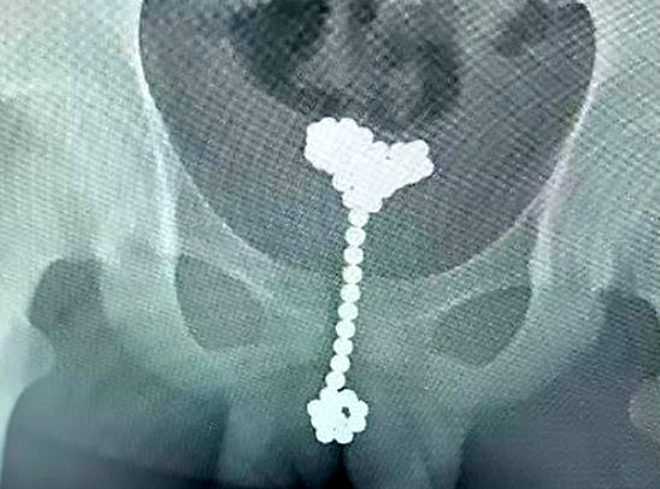

Doğu Çin'in Hubei bölgesinde yaşayan 14 yaşındaki Jiang Hua, cinsel hazzı arttırmak için kullandığı oyuncak yüzünden kendini hastanede buldu.

Doğu Çin'de yaşayan 14 yaşındaki genç, cinsel hazzı arttırmak için kullandığı oyuncaklar yüzünden neredeyse ölüyordu.